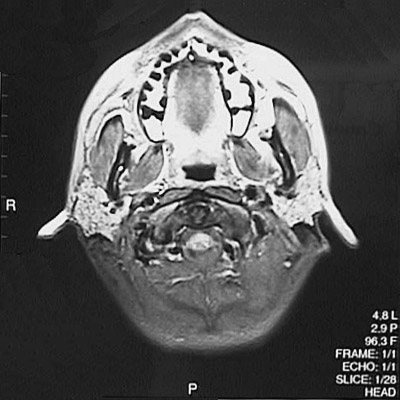

This is a normal axial proton density MRI scan demonstrating the teeth in maxilla and tongue and pharynx and parotid gland and masseter muscle and medial pterygoid muscle and cervical spinal cord.